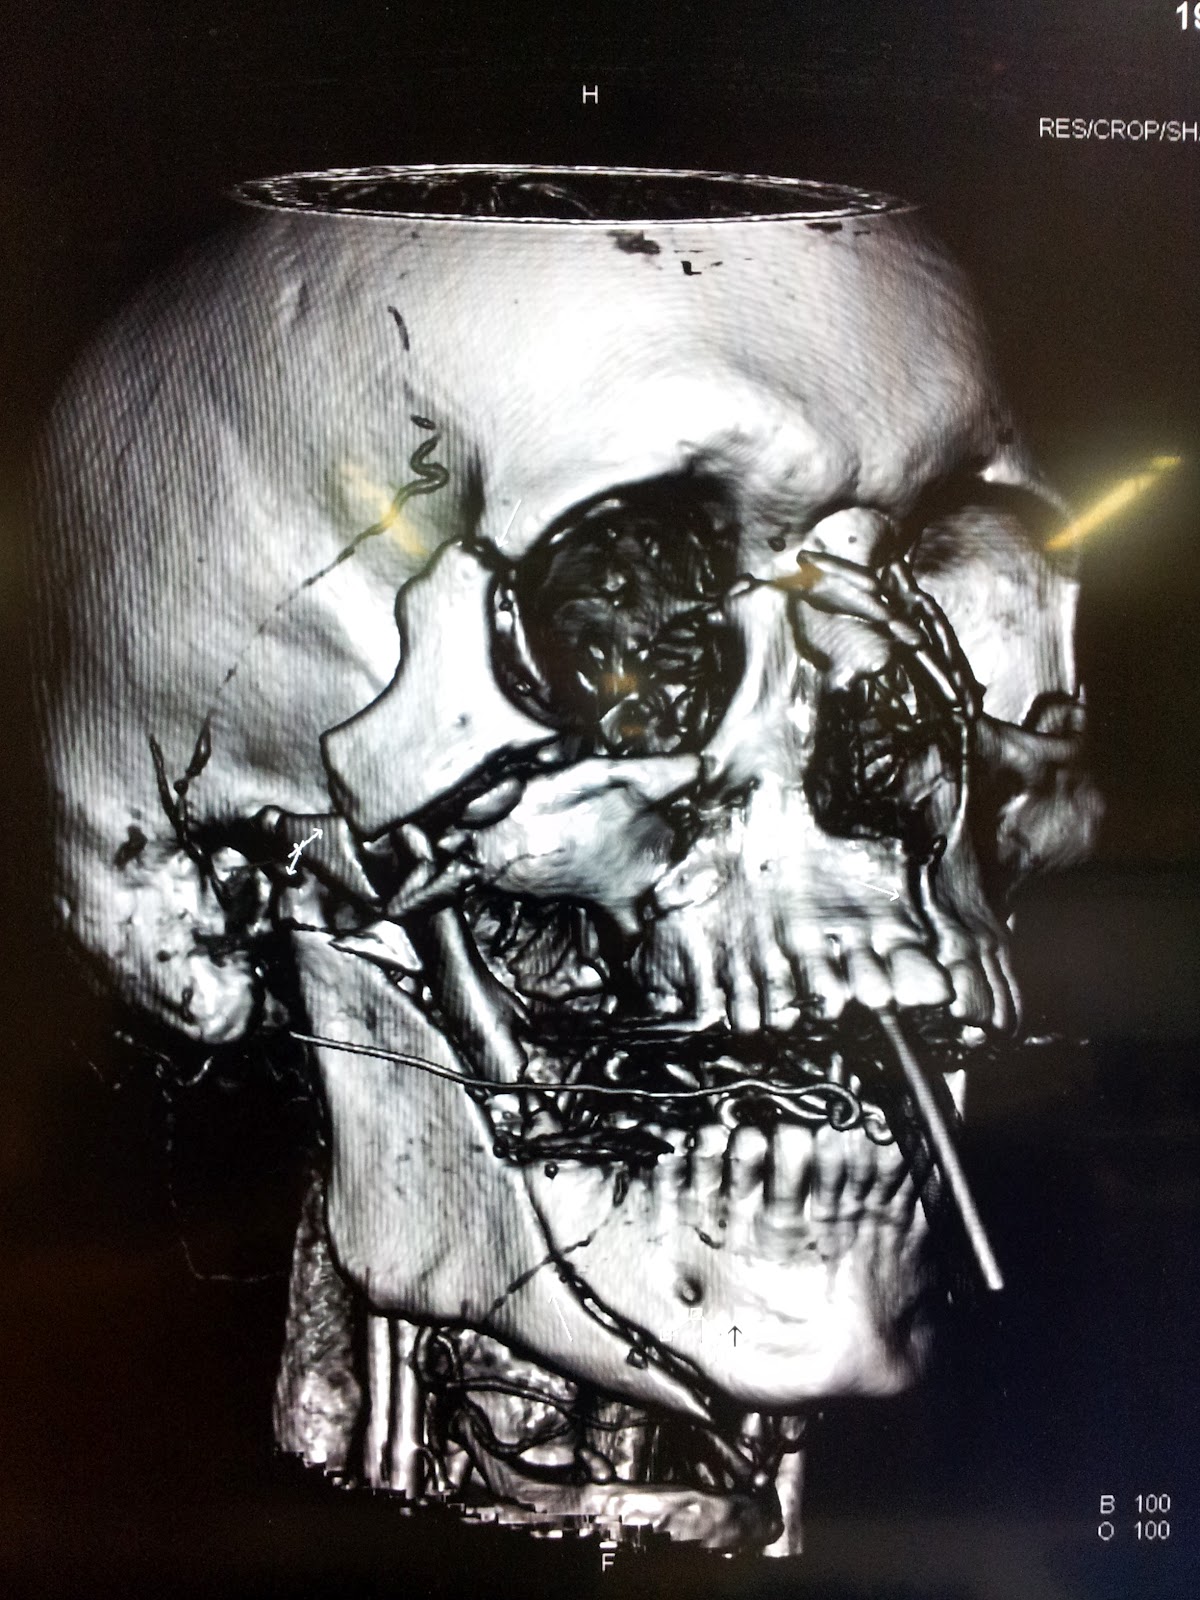

Of course, on my first clinical day, I walk in at 0745 and everyone’s in one of the five trauma rooms. A male bicycle rider vs a truck. Truck wins, every time…..I don’t want to upset anyone with the graphic details, but I spent the morning lead-gowned as an observer in the Interventional Radiology suite watching them coiling hemorrhaging mid-face arteries.. Though I was a complete stranger, the Aussie crew couldn’t have been more professional or accommodating; even allowing me to shoot pictures of them busy at their life-saving work….And what an amazing privilege, to be allowed a glimpse inside their fascinating environment…. Here are a few shots, while still trying to keep it family friendly…

| CT 3D, Lots of facial trauma if you know where to look… |

For the Medical people following along, I have to say, it’s been a wonderful and humbling experience to be back in the Tertiary world after 20 or so years.. I’m one of the “senior” team members now, but everyone is extremely helpful; and luckily, they aren’t expecting me to run the team. Unless I want to, of course…! Teaching Residents again has been very rewarding; I have seen a lot over 20 years it seems……The clinical conditions are similar, but the management has changed somewhat. We are using lots of pressors, Adrenaline and Noradrenaline (no “Epi” down under!), Propofol infusions, lots of Ketamine, even in adults; auto-infusion devices..But no Dilaudid, IV Benadryl, Lorazepam or Quinalones…Ultrasound guided everything..central lines, arterial lines…Very high acuity, very invasive and intellectually challenging for sure! And the 64 slice scanners with near instantaneous 3-D reconstruction provide very rapid confirmation, or humiliation of your clinical diagnoses…